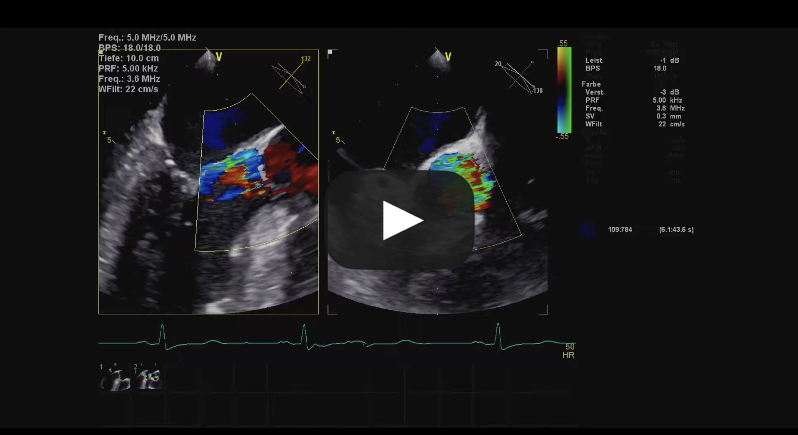

Bicuspid Aortic Valve Repair

Source: Cardiac Research & Education Saar GmbH, used with permission.

Tricuspid Aortic Valve Repair